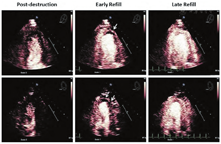

心肌灌注成像已被用于评估心肌局部缺血和存活心肌等多种场合。静脉输注或小剂量注射UEA的VLMI成像已被用于在20~30 Hz的帧频下检查心肌血流量和容积,这被称为实时心肌声学造影(RTMCE)。给予简短的高机械指数脉冲以清除心肌造影剂,然后在收缩末期图像上分析再填充过程(视频8和9;在www.onlinejase.com获取),这一技术已在多巴酚丁胺或踏板、踏车运动负荷试验中临床应用于数千名患者[16,42,45,46,49,57,65,66]。

视觉定性分析更容易学习和减少劳动强度(图7和图8,视频10;可从www.onlinejase.com获得)。以下经验法则可用于结果判读:使用2D超声探头进行静息再充填应该在高机械指数脉冲闪击破坏后5 s内,在负荷状态下应2 s内再充填(视频6和7;在www.onlinejase.com获取)[1]。

在任何形式的负荷成像过程中,二维成像平面的再充填应该是一致的,并且静息状态在5 s内、负荷状态下在2 s内再充填。图11显示了高机械指数脉冲后正常的静息状态和负荷后的再充盈情况。图12和图13是在多巴酚丁胺负荷期间不同冠状动脉区域中诱导的心肌灌注缺损的示例。